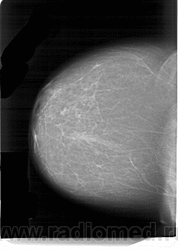

Со старением железистая ткань постепенно исчезает: прозрачность жировой ткани становится преобладающей с несколькими каркасами, связанными с опорными волокнистыми структурами.

Жирная (не плотная) грудь

Умеренно плотная грудь

Плотная грудь

Маммограммы представляют собой изображения структур, проецируемых на плоскость: плотная грудная маммограмма, следовательно, состоит из многих других структур, которые необходимо проанализировать, чем более жирная, пустая грудь. По этой причине диагностировать рак молочной железы труднее для моложе, чем для пожилых женщин.

Нажмите на миниатюрные картинки, чтобы получить увеличенный размер.